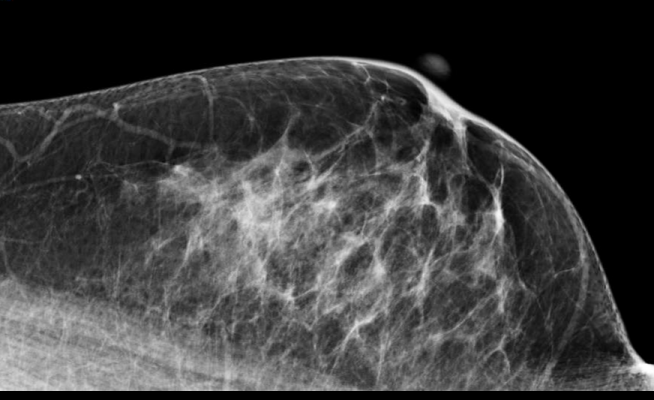

Study authors retrospectively analyzed 46,288 consecutive screening mammograms performed at UCSF for 22,792 women. The examinations were divided into three groups: those interpreted without comparison with prior mammograms, those interpreted in comparison with one prior examination, and those interpreted in comparison with two or more prior examinations.

The recall rate for mammograms interpreted without comparison to prior examinations was 16.6 percent, whereas that for mammograms compared to one prior examination was 7.8 percent, and that for mammograms compared to two or more prior examinations was 6.3 percent.